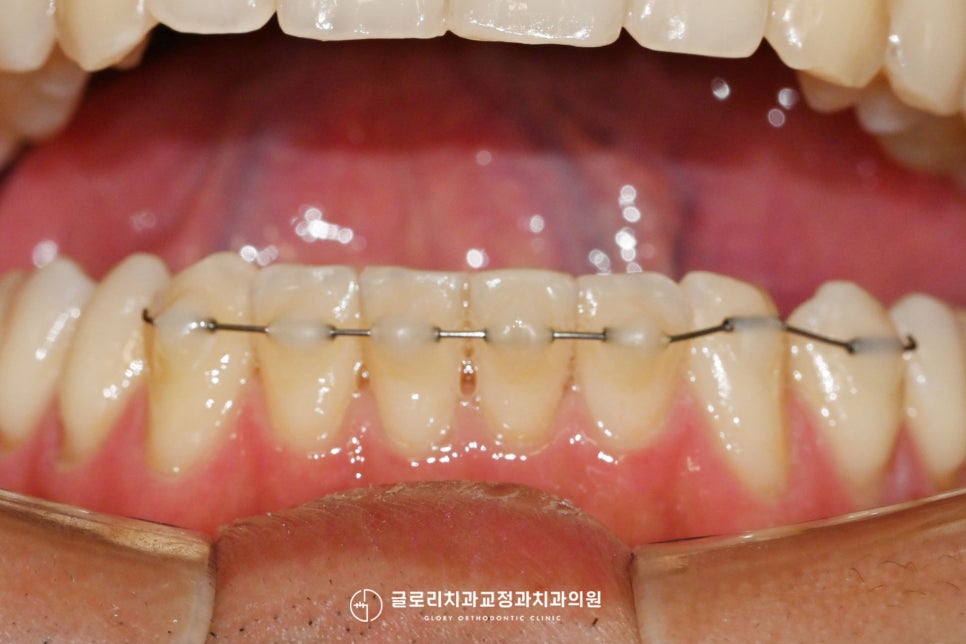

3. 진행 과정

이렇게 망우동 치과 에서 붙여드린

MTA의 모습을 보실 수 있는데요.

이전에 자주 활용되었던 금속 브라켓 방식과

비교해 보면 브라켓 크기부터 작게 만들어져

아예 다른 느낌으로 훨씬 더 심미성이 우수한데요.

부드러운 표면을 가지고 있어

구강 내 다른 조직들이 다칠 위험이 적으며

불편한 감각이 생길 가능성도 적은 편으로

아직은 이렇게 배열이 잘 맞지 않은 느낌이라

조금 더 시간을 두어 지켜보아야겠습니다.